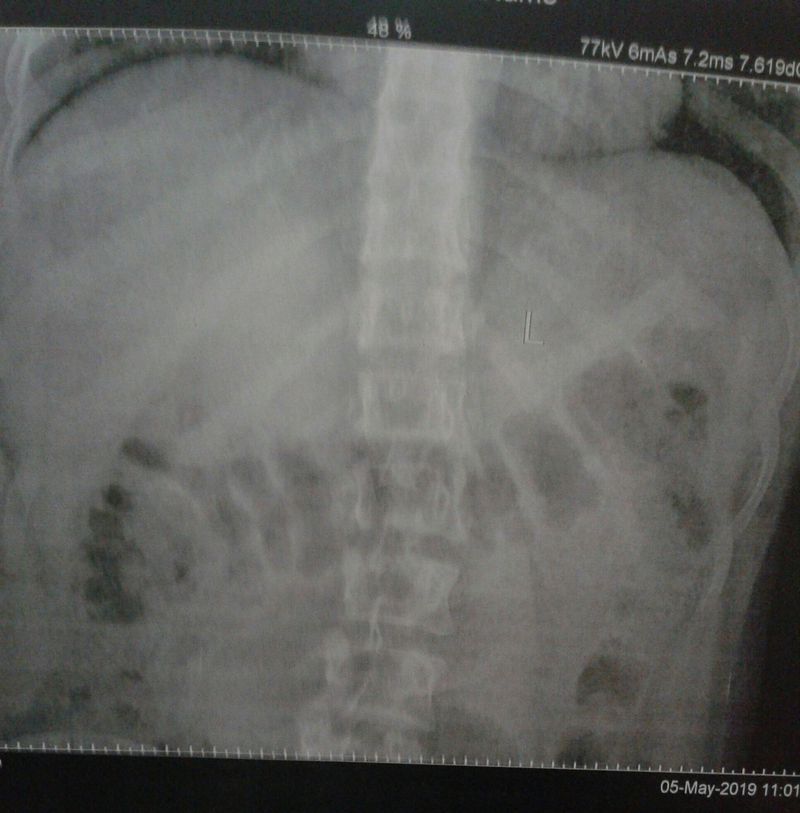

lumbur region

your diagnosis?

Lumbar

Anteriorposterior